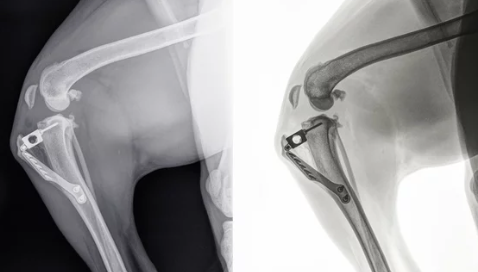

수술 방법은 손상된 십자인대를 제거하고 새로운 인대로 대체하는 과정을 포함합니다. 이를 위해 환자 자신의 힘줄을 사용하는 자가 이식술이나 타인의 힘줄을 사용하는 동종 이식술, 인공 물질을 사용하는 합성 이식술 등 다양한 방법이 있습니다. 수술은 일반적으로 관절경을 사용하여 수행되며, 이는 더 작은 절개를 통해 수술을 가능하게 하여 회복 시간을 단축시키고 흉터를 최소화합니다.